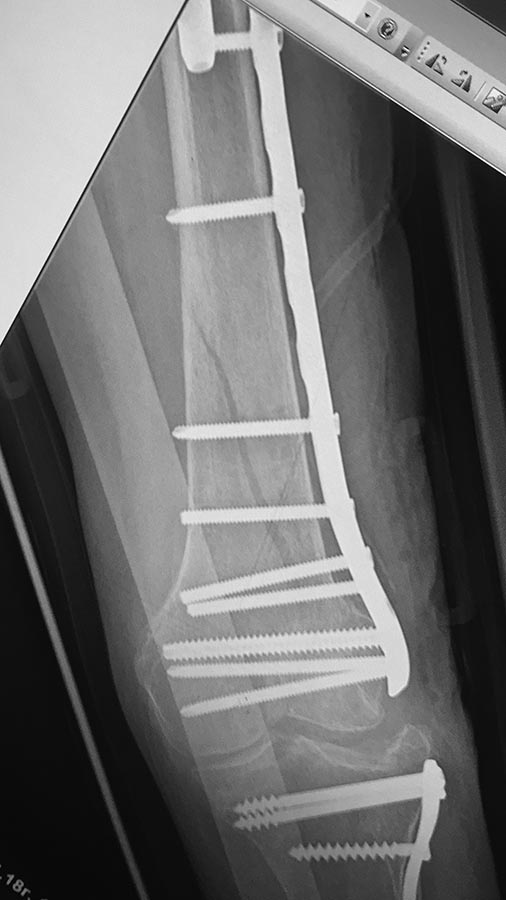

[Ortho] Сросшийся чрезвертельный и перелом н\3 бедра

Мыщелки2